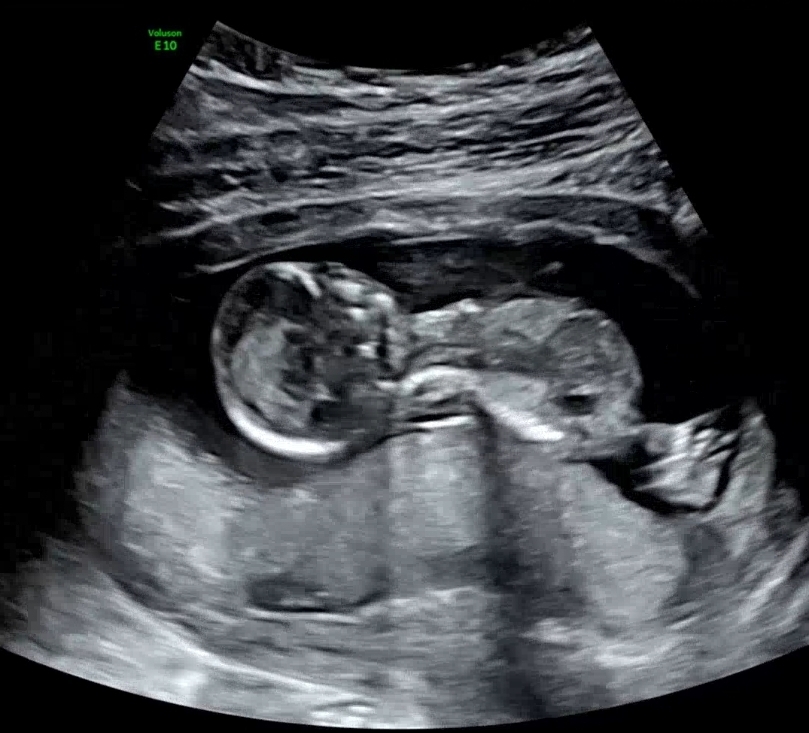

각도법 봐주실 분 계신가용😍😍

너무 궁금한데 부탁드려요💗💗복받으실거예요!!🍀🍀

돌기가 잘 안 보이는 사진이예요

잘은 모르지만 공주님..? 아닐까싶네요 ㅋㅋ